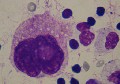

3.2. La leucémie mégacaryocytaire (LAM 7).

Promégacaryocyte : cytoplasme réduit, biploïde avec 2 gros nucléoles. Cette forme blastique est fréquente en cas de LAM7, au niveau du myélogramme. Chat.

Elle est également rare, elle se diagnostique par une quantité de mégacaryocytes supérieure à 30%, au niveau du myélogramme. Souvent, des micromégacaryocytes sont visibles dans la circulation, mais ils sont parfois difficiles à distinguer d'un lymphocyte. Il faudra bien rechercher les excroissances granuleuses neutrophiles ou azurophiles du cytoplasme. Notons encore que ces micromégacaryocytes ne sont pas pathognomoniques et qu'on les rencontre aussi lors de maladies myéloprolifératives. A la différence de la thrombocythémie essentielle, il n'existe pas nécessairement de thrombocytose lors de LAM 7. Une chimiothérapie combinée de type COAP peut être entreprise, mais le pronostic est sombre.